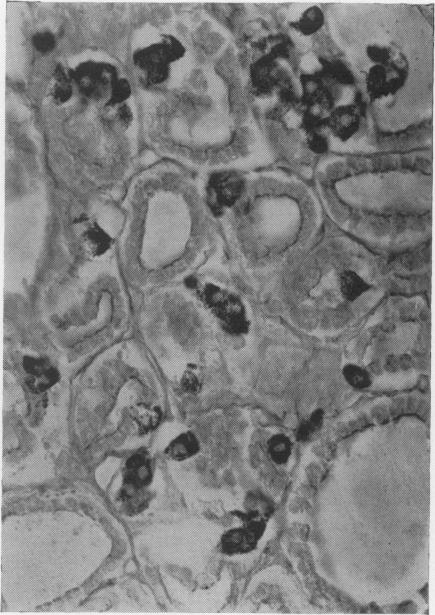

In 1962 Copp proposed the existence of a hypocalcaemic hormone. Subsequent studies have shown him to be right. Calcitonin is a potent inhibitor of bone resorption. By its action it lowers systemic blood calcium. It is secreted in response to hypercalcaemia by a distinct endocrine system within the thyroid in mammals and within the ultimobranchial bodies in fish, amphibia and reptiles. The active principle from pig has now been isolated and found to be a polypeptide composed of thirty-two amino acid residues. Together with parathyroid hormone, the hormone provides precise regulation of calcium concentration in the blood and controls bone remodelling and mineral turnover. Calcitonin in man may be secreted in excessive amounts by medullary carcinoma of the thyroid. In addition, aberrations in its secretion may play a role in pseudohyper-parathyroidism and ostepetrosis.

1962年,科珀提出存在一种降钙素。随后的研究证明他是正确的。降钙素是骨吸收的有效抑制剂。通过其作用,它可降低全身血钙水平。在哺乳动物中,它由甲状腺内一个独特的内分泌系统分泌以应对高钙血症;在鱼类、两栖动物和爬行动物中,则由后鳃体分泌。现已从猪体内分离出活性成分,发现它是一种由32个氨基酸残基组成的多肽。该激素与甲状旁腺激素一起,精确调节血液中的钙浓度,并控制骨重塑和矿物质代谢。人类的甲状腺髓样癌可能会分泌过量的降钙素。此外,其分泌异常可能在假性甲状旁腺功能亢进和骨石化症中起作用。